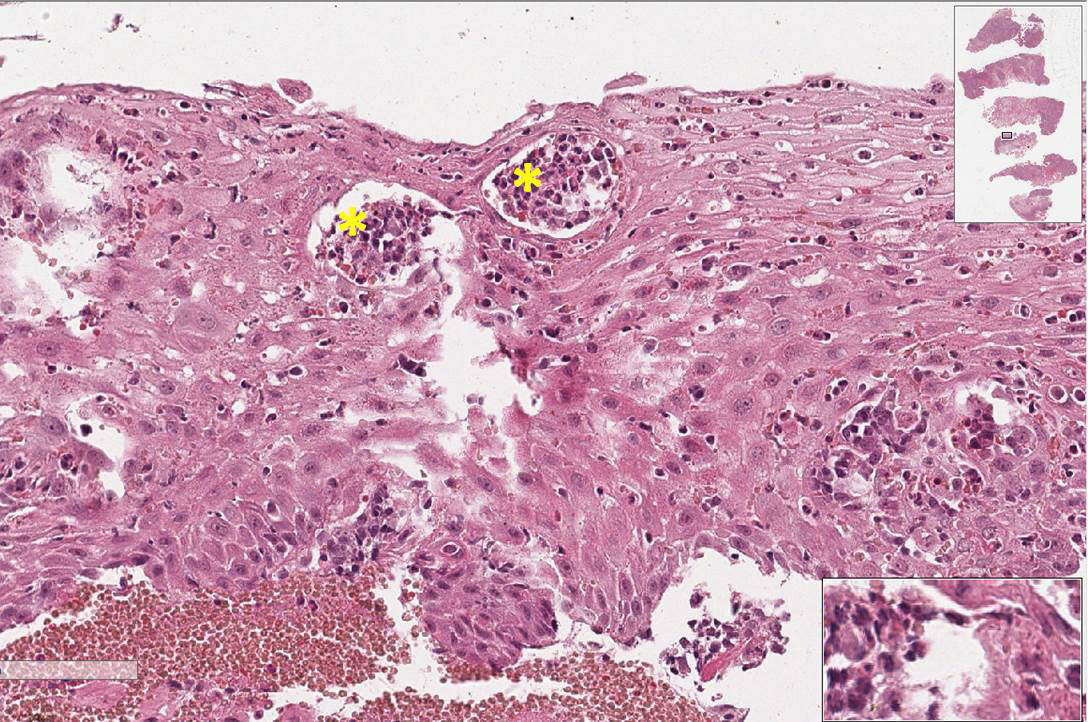

Fragmento de mucosa revestido por tecido epitelial estratificado pavimentoso paraceratinizado, apresentando hiperplasia pseudoepiteliomatosa (sensação de que o epitélio “invade” o tecido conjuntivo) e áreas de micro abcessos (pequenas coleções de neutrófilos e piócitos superficiais). No tecido conjuntivo subjacente, observa-se a formação de granulomas que apresentam externamente fibroplasia, seguida por um colar de linfócitos, e mais centralmente observam-se um aglomerado de macrófagos epitelióides (núcleo claro e alongado e as células podem apresentar um arranjo em paliçada ou justapostas umas às outras). Entremeados as células do granuloma observam-se células gigantes do tipo Langhans. Em algumas áreas, principalmente no interior das células gigantes, é possível visualizar os fungos que se apresentam como um espaço negativo (branco) e forma geométrica redonda.

Observar os granulomas compostos por um aglomerado de macrófagos epitelióides, colar de linfócitos e fibroplasia externa assim como a presença de células gigantes fagocitando os fungos. Os microabscessos e a hiperplasia pseudoepiteliomatosa são sugestivos, mas não específicos desta doença.

Paracoccidiodomicose

Os aspectos morfológicos observados (granulomas no tecido conjuntivo, hiperplasia pseudoepiteliomatosa e microabscessos no tecido epitelial) são os mesmos. Essa técnica pe utilizada para evidenciar o Paracoccidioides brasilienses, agente etiológico da paracoccidioidomicose, e confirmar o diagnóstico. Em lâminas coradas por HE nem sempre é possível evidenciar o espaço claro na célula gigante, o qual costuma sugerir presença deste microrganismo.